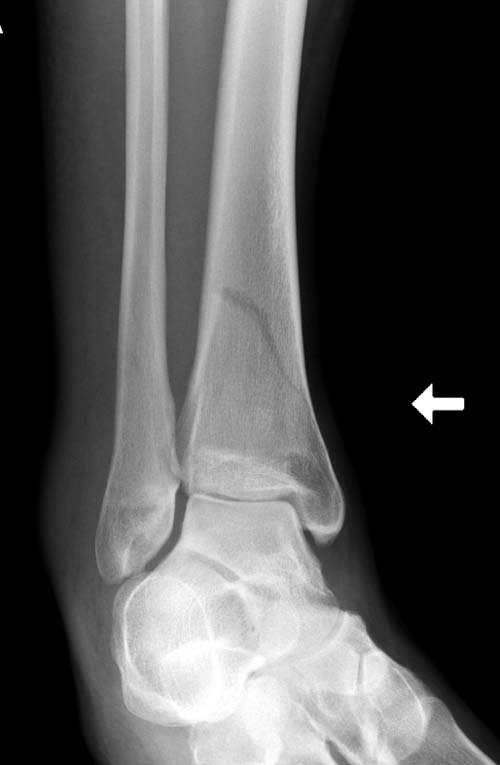

Второй случай в результате скоростной травмы, кроме пилона, вовлечение других органов! Отек при поступлении и открытый перелом на другой стороне. В таких случаях нет смысла спешить, и временный наружный фиксатор на несколько дней. После спадения отека фиксация передне-наружной пластиной. Реабилитация - ранние движения, без нагрузки.